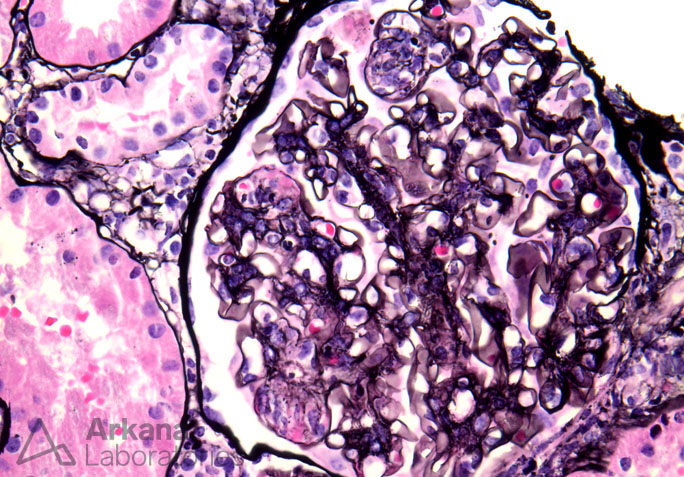

Previous Image Next Image Endocapillary Proliferation in Lupus Nephritis on Jones Silver Like Loading...